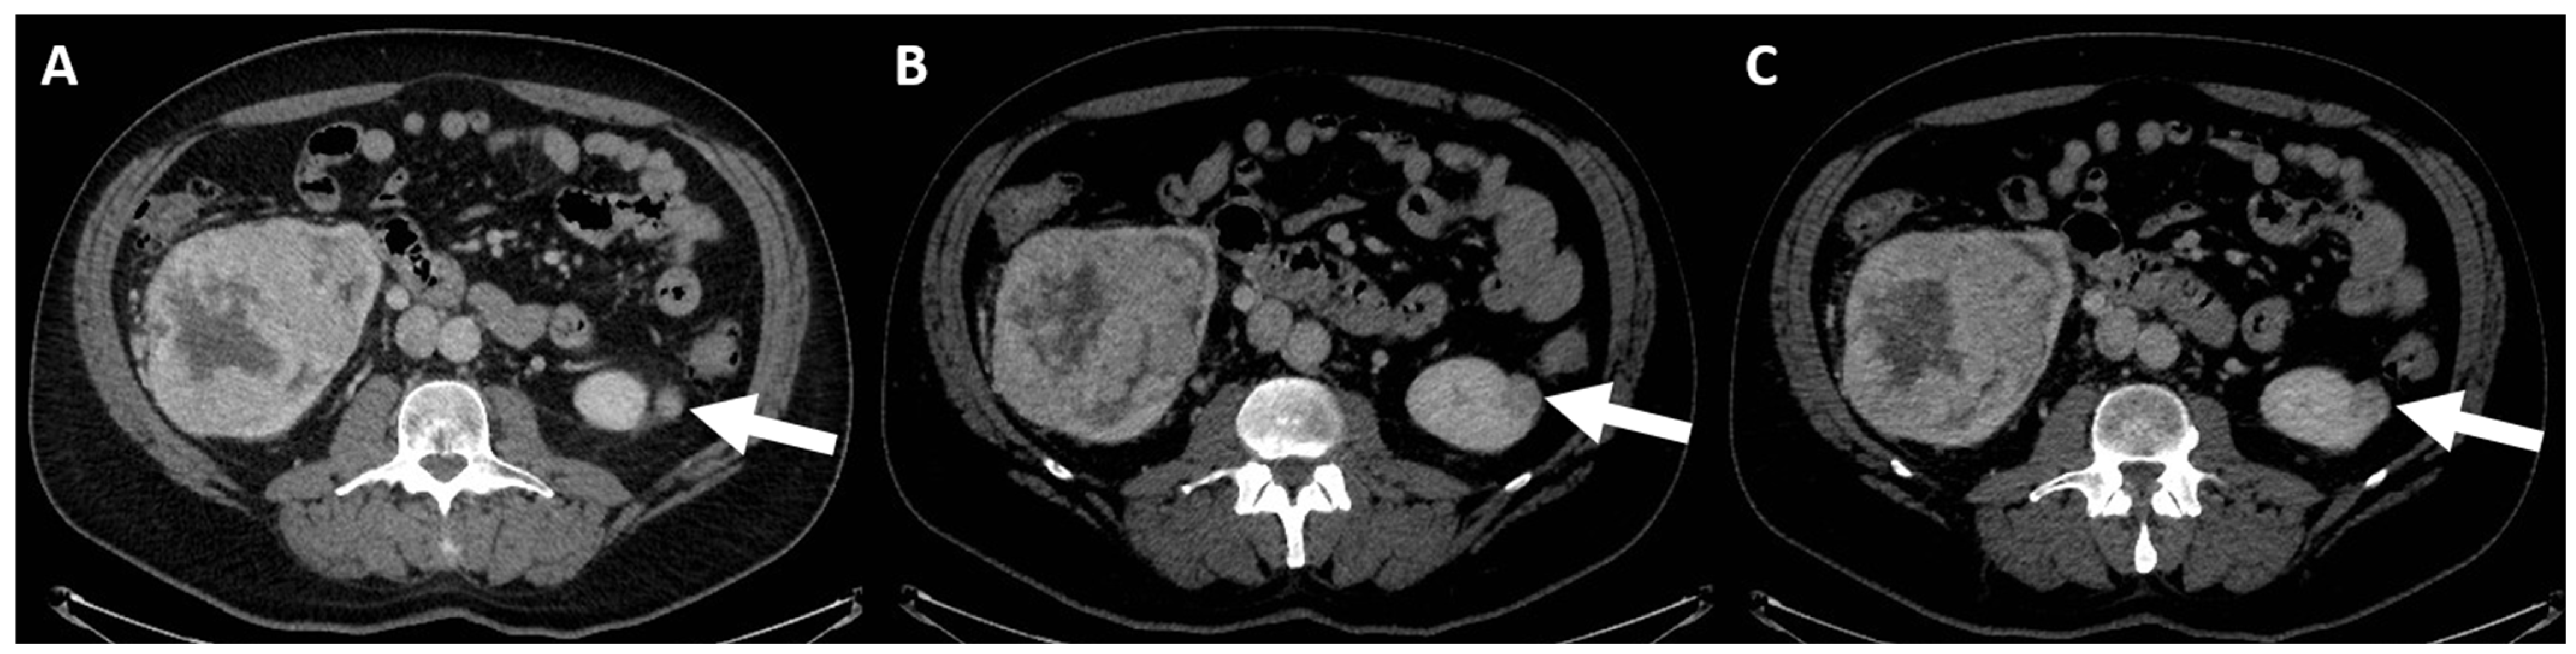

4. Computed Tomography Assessment

4.3. Enhancement